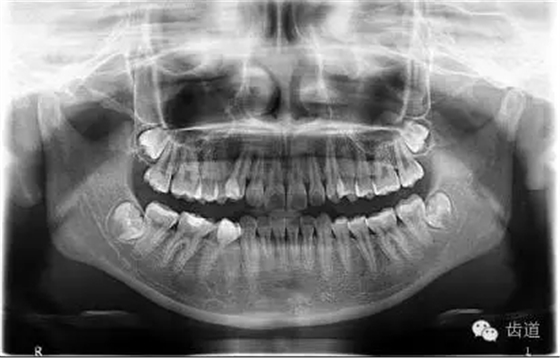

1.術(shù)前全景片

可見(jiàn)37根尖周有明顯透射影像(患者當(dāng)日懷疑第三磨牙阻生問(wèn)題,初診科室為外科,擬行雙側(cè)阻生齒拔除術(shù),故已向行全景片拍攝)

2. 術(shù)前X片

可見(jiàn)37根管影像清晰,根中上三分之二粗大,根尖三分一分為近遠(yuǎn)中兩根管,形態(tài)均呈弧形,根尖周膜連續(xù)性中斷,根尖周透射影明顯